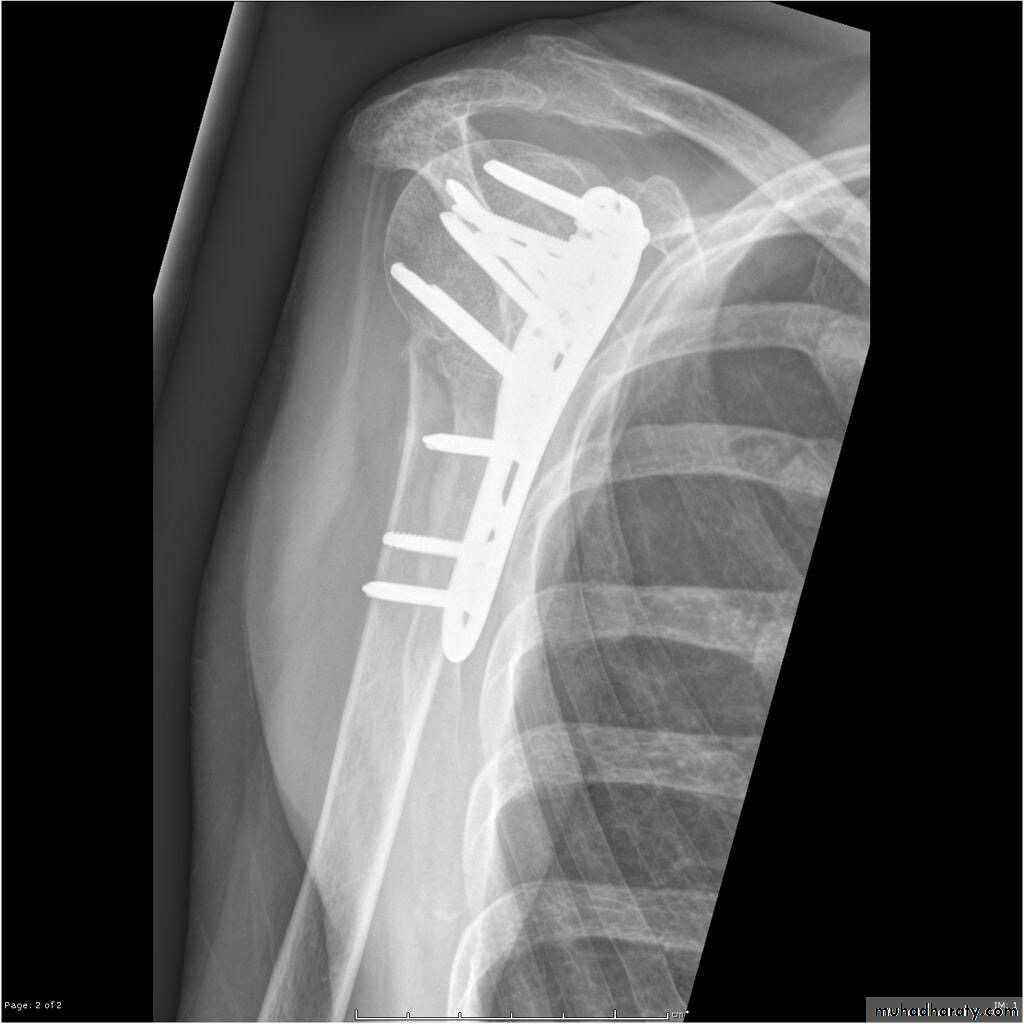

• Close reduction (MUA&sling ) 6weeks and active exercise later if failure

• Open reduction & internal fixation by percutaneous pinning plate and screws or intramedullary nailing21

TREATMENT

22

Plate and screws

23

30

ORIF